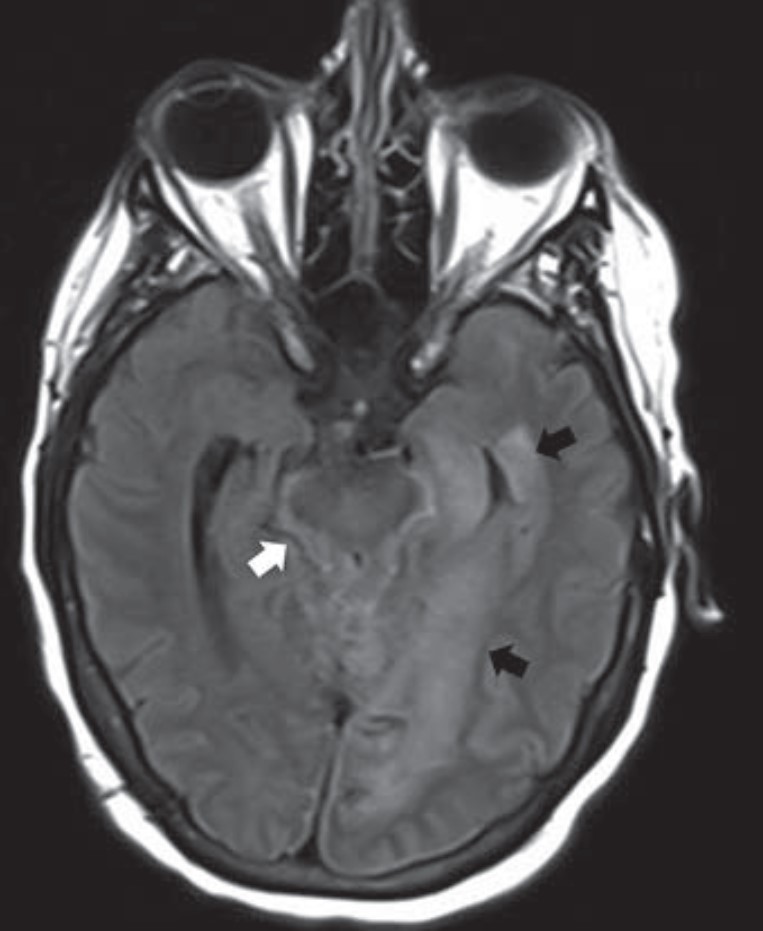

Overview of Imaging Intracranial Infections

The manifestations of CNS infections are myriad, including diffuse (meningitis, encephalitis, ventriculitis), focal (abscess, empyema), and other special presentations, especially in immunocompromised patients. Diagnosing CNS infections is decidedly multidisciplinary, and as “Overview of Imaging Intracranial Infections” points out, radiology’s contribution to the clinical workup of a patient is paramount. The Roentgen Ray Review’s first entry in its Categorical Course Highlight series, this CME credit article focused on key confounders details how CT and MRI with FLAIR sequencing and DWI can focus your differential diagnosis—ultimately streamlining additional testing and management decisions by the clinical team (Fig. 1).